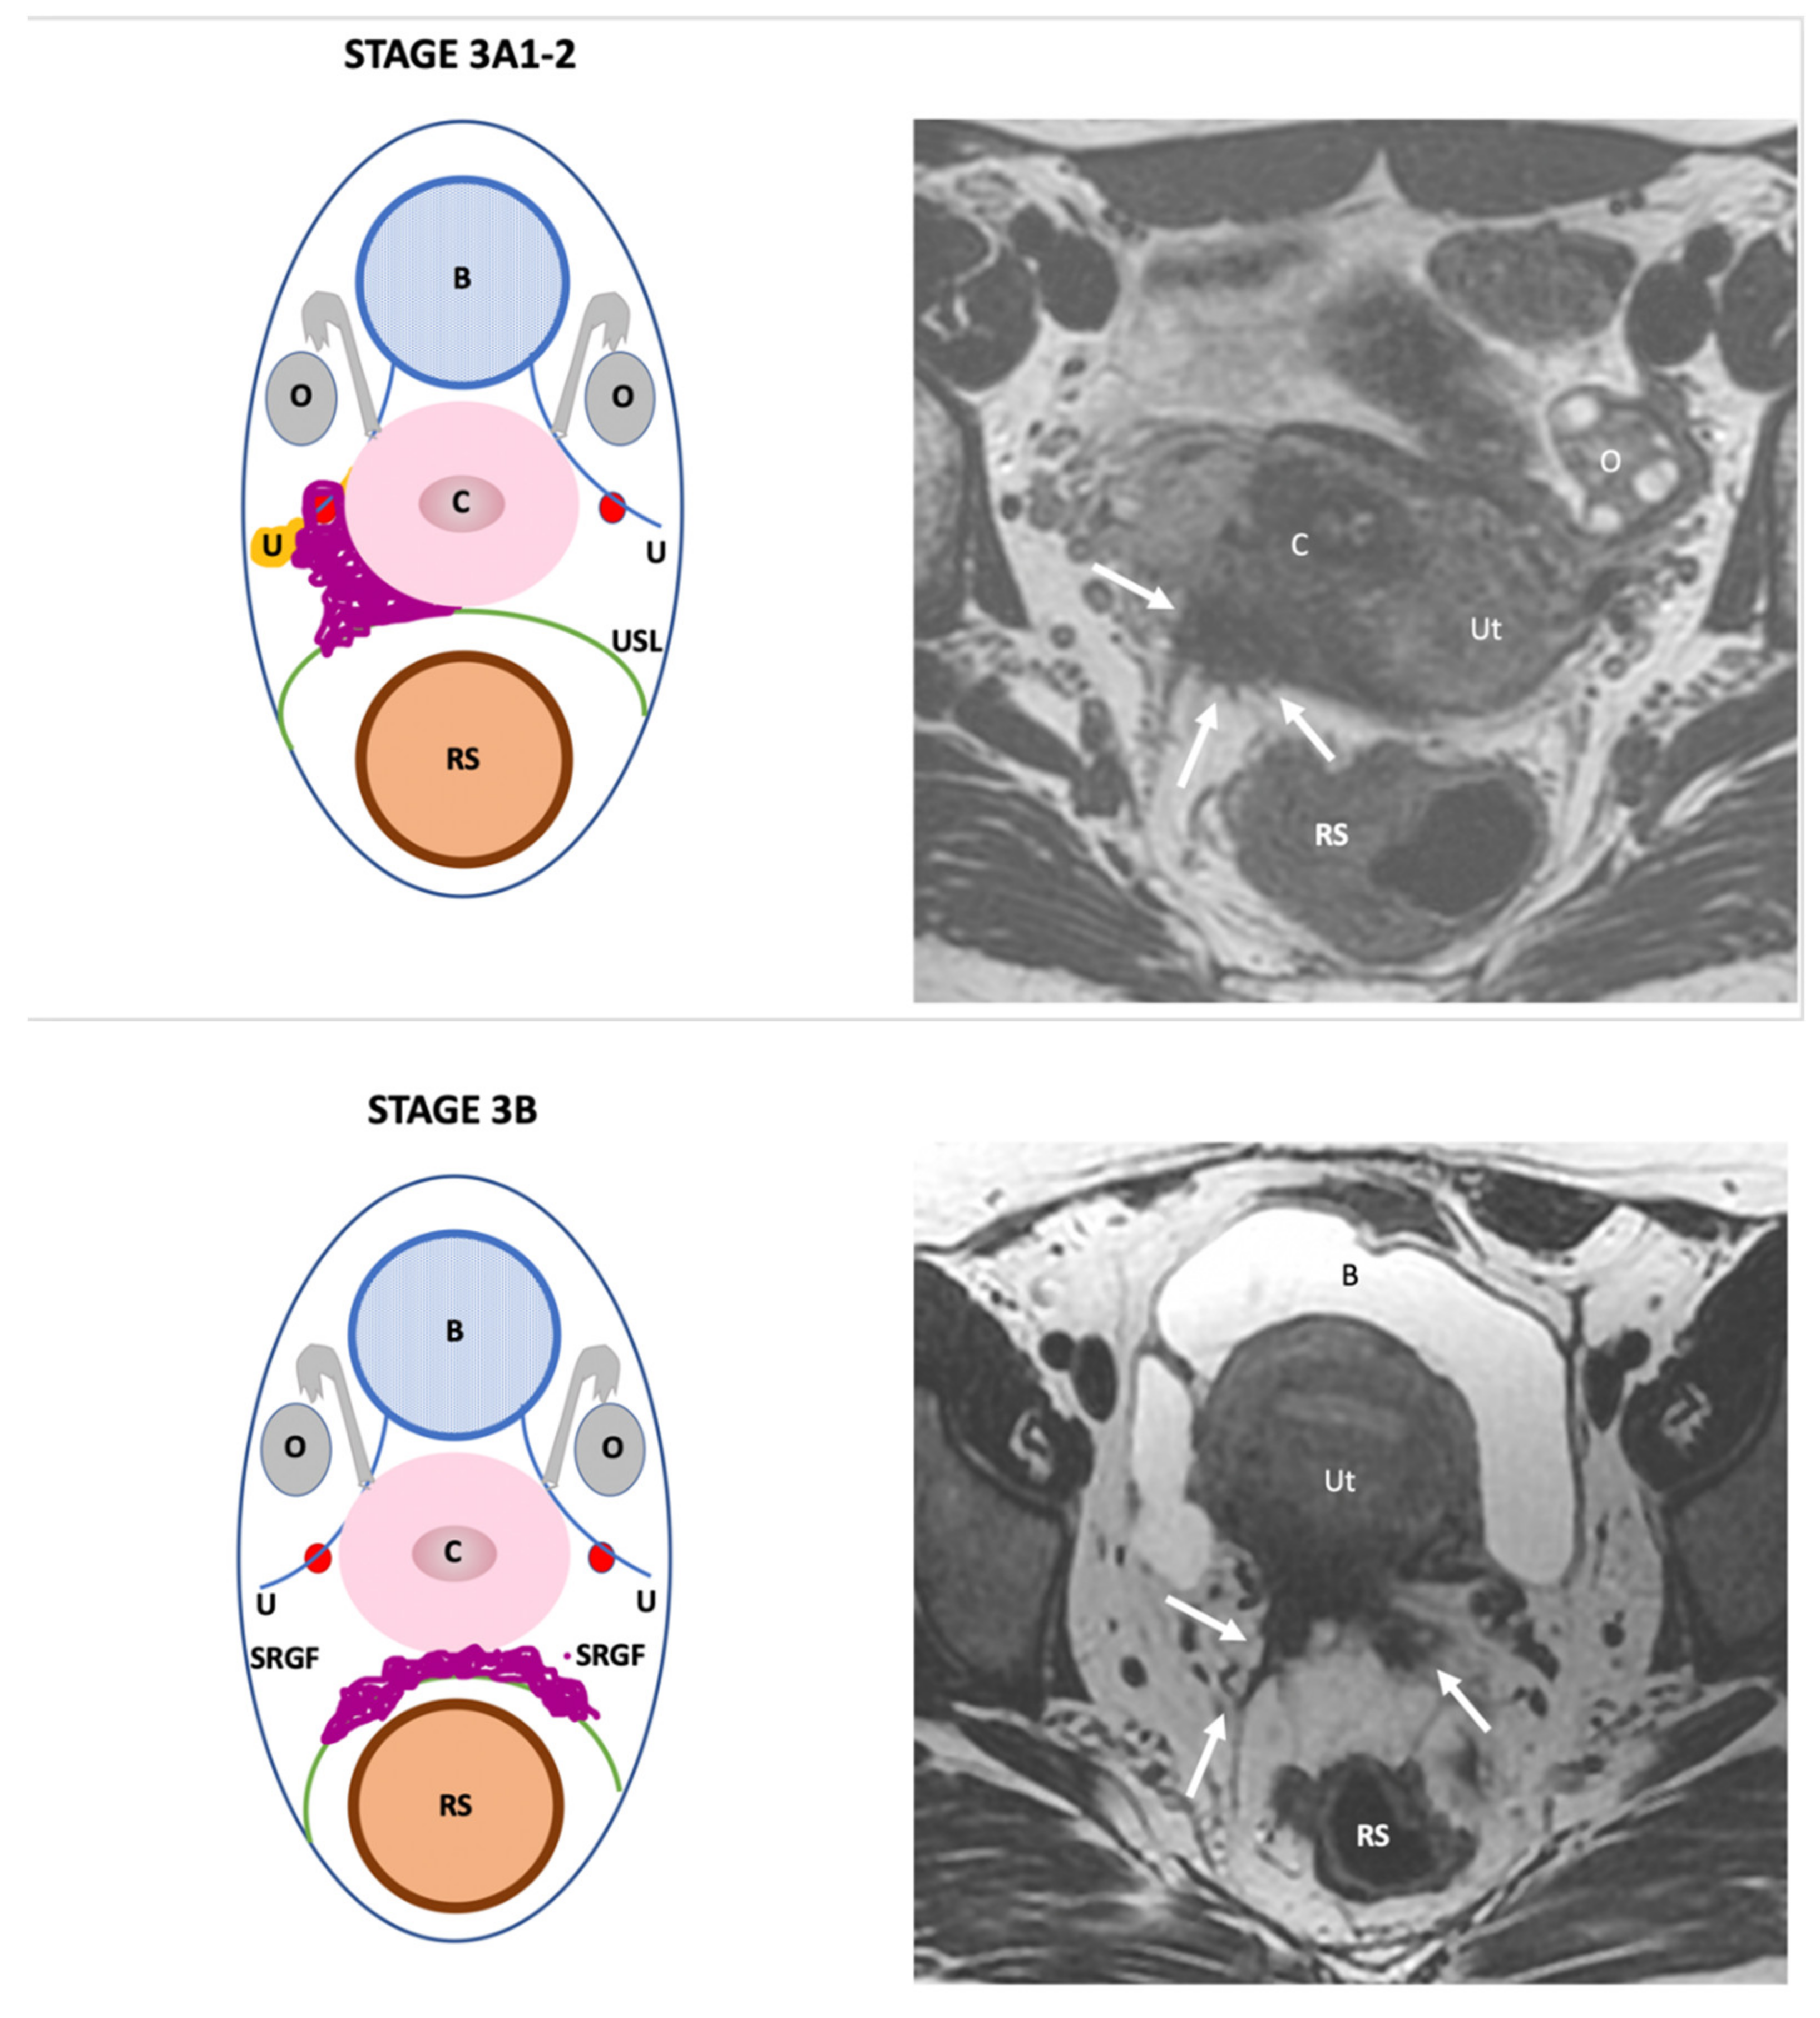

| Endo-Stage MRI | Location | Extent | Risk Stratification |

|---|---|---|---|

| Endo-Stage MRI 0 | Superficial endometriosis |

| Low |

| Endometriosis is strictly confined to the ovaries |

| ||

| Endo-Stage MRI I | Endometriosis is strictly confined to the retrocervical area |

| |

| Endo-Stage MRI II | Endometriosis invades beyond the retrocervical area, but not to the pelvic side-wall |

| Endo-Stage MRI III | Endometriosis extends to the pelvic side-wall and/or causes hydronephrosis or non-functioning kidney |

| Intermediate |

| Endo-Stage MRI IV | Endometriosis has involved the bladder or rectosigmoid colon |

| Endo-Stage MRI V | Multiple deep endometrioticlocations |

| High |